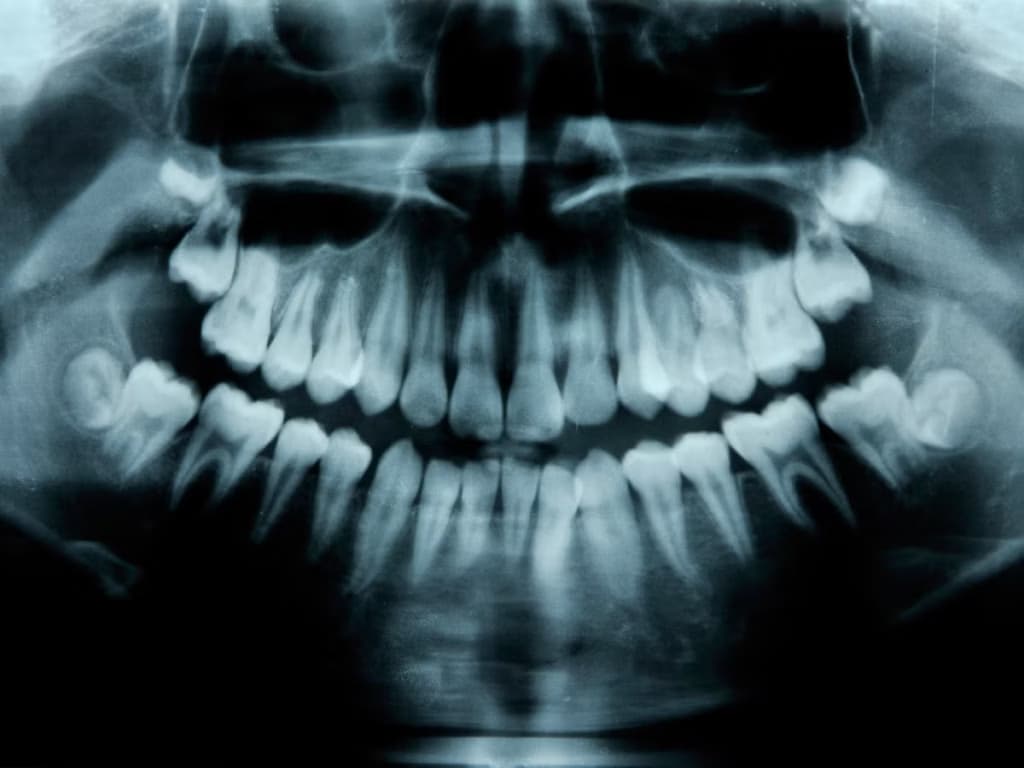

Вчені знайшли спосіб виростити нові зуби у дорослих людей

Дослідницька група з Японії під керівництвом Katsu Takahashi розпочала клінічні випробування препарату, здатного стимулювати зростання нових зубів у людей. Препарат впливає ген USAG-1, який, як встановили вчені, обмежує природне зростання зубів.

Дослідження ґрунтується на відкритті, що у людей існує зародковий третій набір зубів, який зазвичай не розвивається. Дане відкриття підтверджується наявністю гіпердонтії у 1% населення – стану, при якому зростає більше стандартного набору зубів.